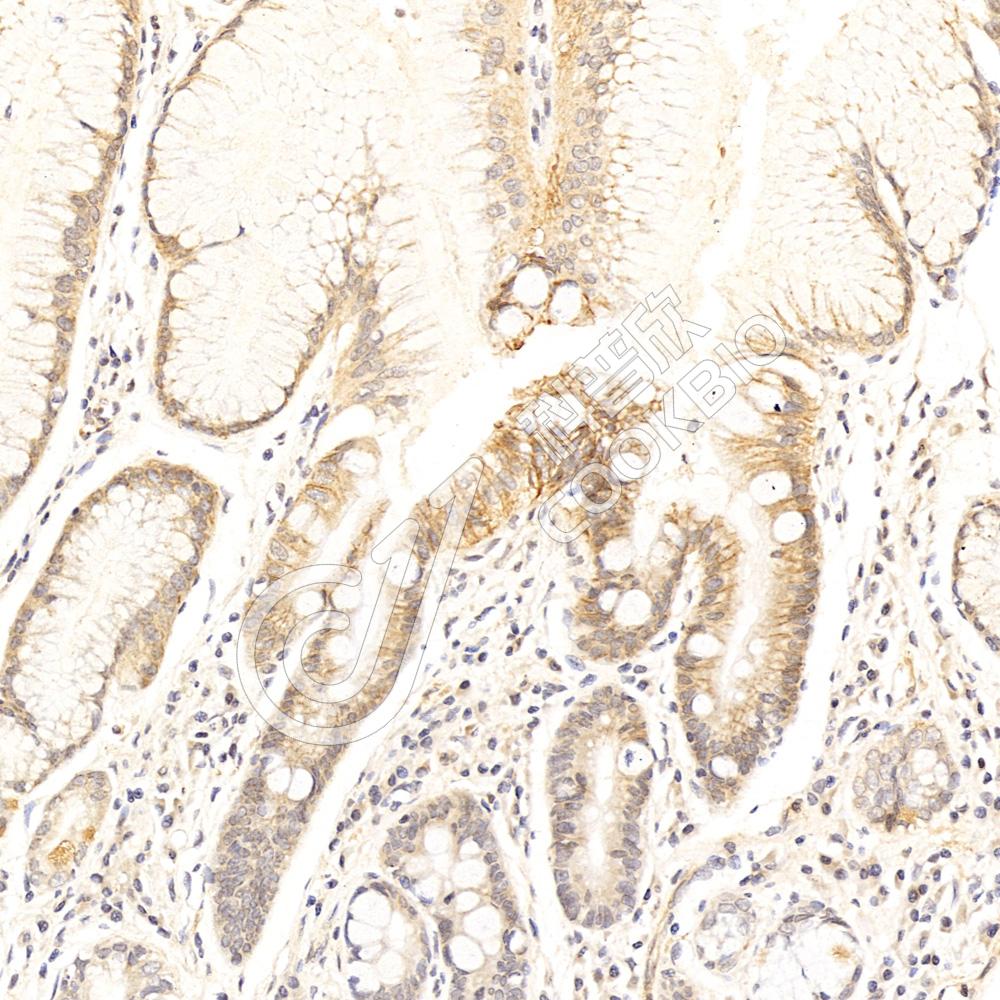

IHC检测Skp1蛋白(货号 K1333690).

样品: 人食管癌, 4%多聚甲醛 (货号KSG1101) 固定12-24小时.

抗原修复: 柠檬酸抗原修复液(干粉, pH 6.0) (KSG1201), 98℃, 20分钟.

—抗: 1: 2300稀释, 4℃ 孵育过夜.

二抗: S-vision免疫组化多聚二抗(山羊抗兔),即用型 (货号KB3906), 室温孵育20分钟.